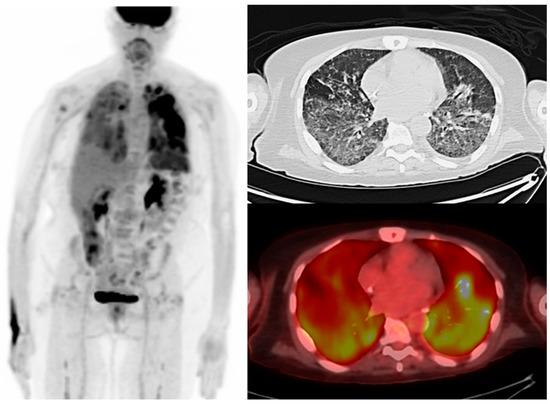

This non-infectious process is a result of CAR T-cell cytokine release and must be promptly treated. It presents with nonspecific clinical and radiological signs indicative of alveolar damage, and can induce hypoxia in severe cases [67]. It is managed with anti-IL-6 agents, PD-1/PD-L1 and CTLA-4 inhibitors and supplemental oxygen, and mechanical ventilation in severe cases [70] (Figure 5).

Figure 5.

A 65-year-old man with relapsed multiple myeloma. Maximum intensity projection, axial CT, and fused PET/CT showing diffuse bilateral FDG-avid ground-glass pulmonary opacities and interlobular septal thickening, greater in the lower lobes on FDG PET/CT obtained post-CAR T-cell therapy suspicious for pneumonitis in the context of cytokine release syndrome.